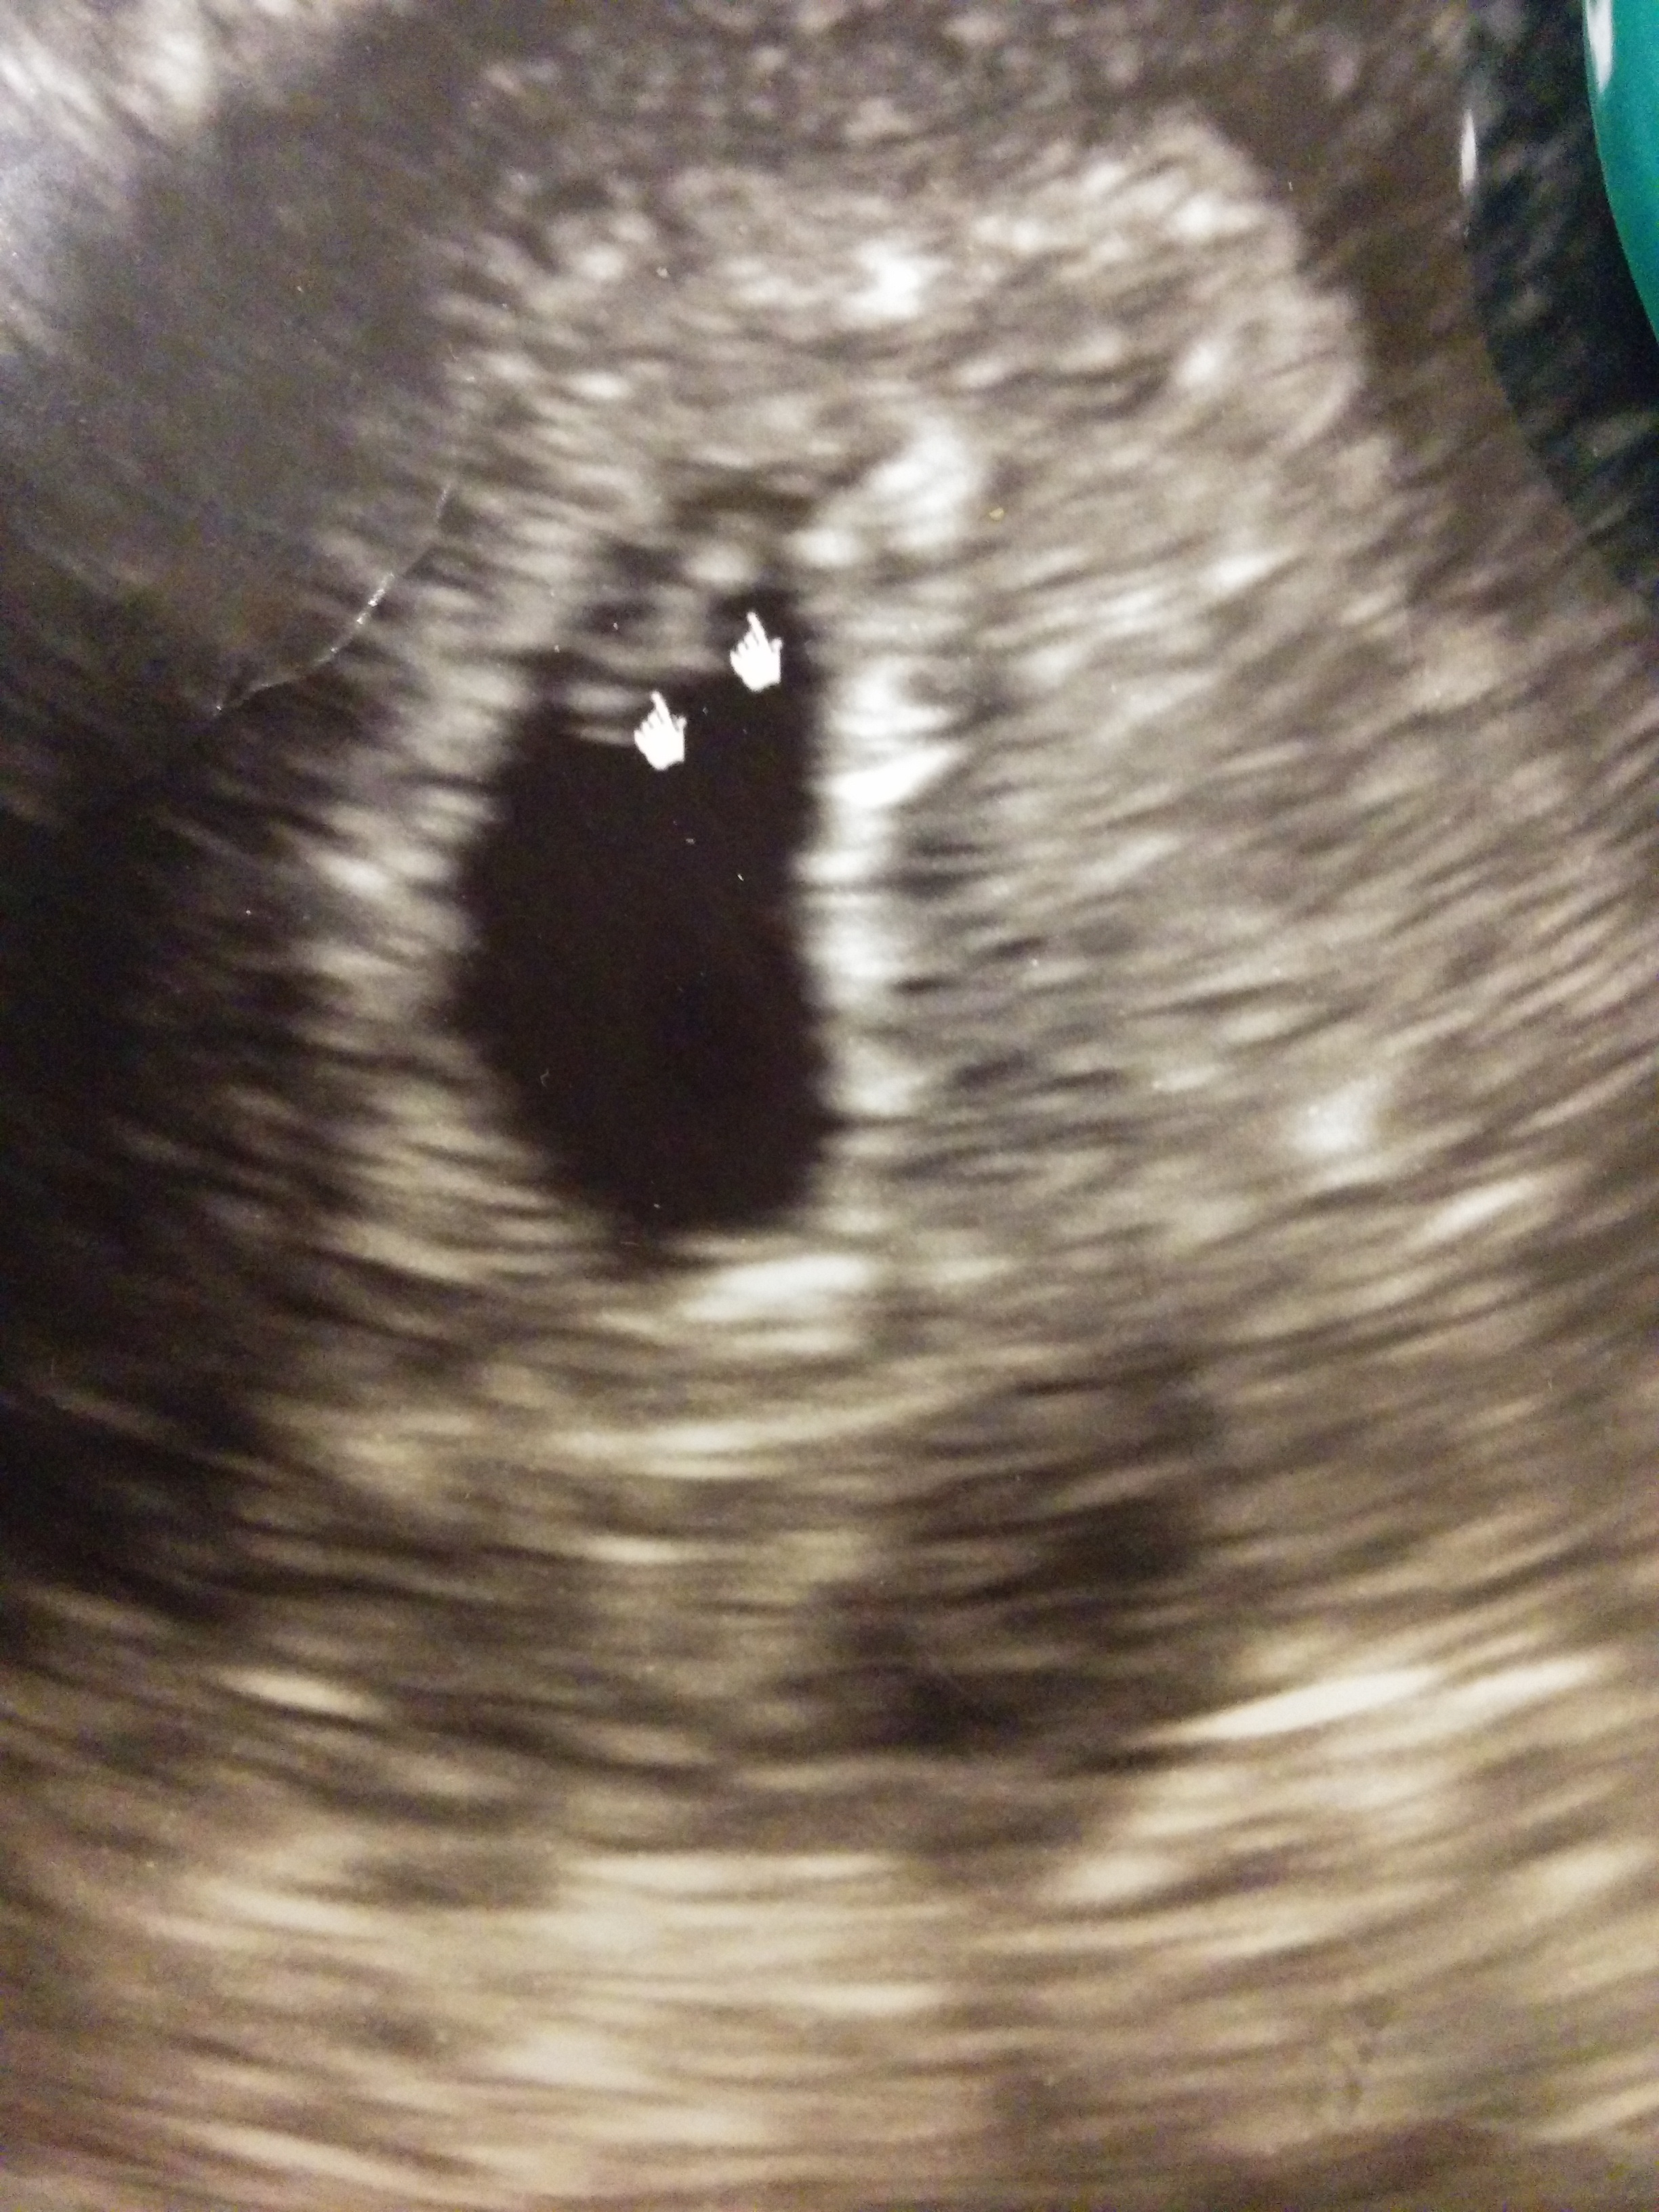

here is my vaginal ultrasound at 6w1d. hoping it works for twins and get a few guesses! Thanks ladies!!

the placenta position is what we are looking at. did the tech tell you where the placenta was? :)